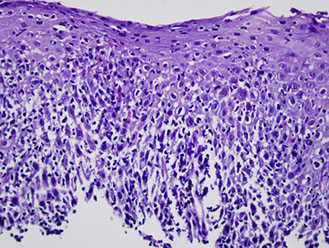

mixed acute and chronic inflammatory cells in the epithelium and lamina propria along with reactive epithelial changes. Note basal and supra-basal cell hyperplasia and elongation of the lamina propria papillae. Inflammation is seen both within the epithelium and in the lamina propria.

GERD histology

An important histologic feature of reflux esophagitis is the elongation of lamina propria papillae to reach as high as the top 1/3 of the squamous epithelial thickness. Focal surface erosion is also seen at the left upper corner.